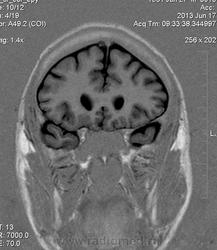

Мужчина 32 лет. Из анамнеза: перинатальное повреждение ЦНС, ДЦП, дизартрия, правосторонний верхний монопарез. С 16 лет приступы эпилепсии.

Аплазия прозрачной перегородки. Шизэнцефалия с открытыми краями в лобно-теменной области слева. Шизэнцефалия с закрытыми краями в лобной области справа? Утолщение коры по контуру расщелин и в области глазничной извилины правой лобной доли. Микрогирия? Гиперостоз костей свода черепа. Уважаемые коллеги, возможно я ошибаюсь, или есть еще аномалия?

сочетания отсутствия прозрачной перегородки и дисплазии ( разно степени выраженности) зрительных неровов  указывает на септоптическую дисплазию-нарушение развития в области средней линии , сопровождается мнггими другими структурными аномалиями, чаще шизэнцефалией.

Спасибо. Как тогда лучше сформулировать заключение? МР-картина кортикальной дисплазии : двусторнняя шизэнцефалия с утолщением коры по контуру расщелин, микрогирия в лобной области справа, очаг гетеротопии серого вещества в области  глазничной извилины правой лобной доли. Признаки септооптической дисплазии (гипоплазия зрительных нервов, аплазия прозрачной перегородки). Лиссэнцефалии не вижу. Есть сомнения по поводу шизэнцефалии справа (может быть я запуталась в микрогирии и мерещится шизэнцефалия?) Нет ли какой либо анамалии развития черепа?

На мой взгляд, полимикрогирия двусторонняя (конвекситальные отделы дорзальных отделов лобных долей и частично теменных, а также в базальном отделе полюса правой лобной доли) + закрытая шизенцефалия левой лобно-теменной области. Аплазия прозрачной перегородки (как признаки лобарной голопрозенцефалии).